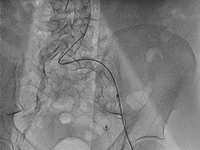

Przykład postępowania w przypadku guza II kości śródstopia pierwotnie podejrzewanego jako przerzut raka pęcherzykowatego tarczycy 40 i 20 lat po całkowitej tyroidektomii

Example of management of metatarsal bone II tumor originally suspected of having metastatic thyroid follicular cancer 40 and 20 years after total thyroidectomy